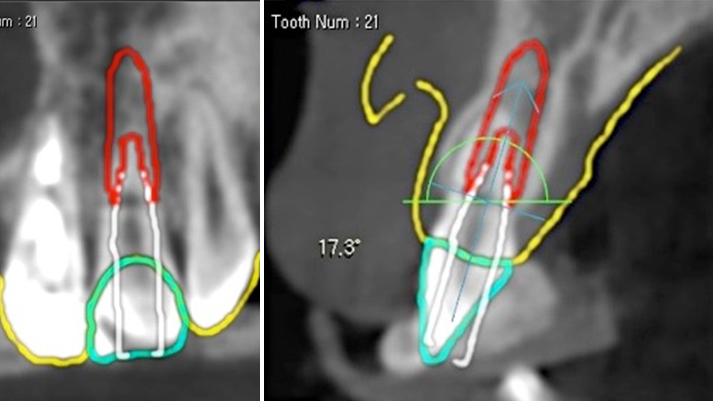

Clinical case: Extraction, immediate placement & loading using

R2GATE solution in aesthetic zone

- Courtesy of Dr. Jong-Cheol Kim, Korea-

Dr. Jong Cheol Kim, immediate loading, digital guided surgery, Digital ONE-DAY Implant, maxillary anterior, #21, guided surgery, immediate loading, AnyRidge, R2GATE, Mega ISQ, MEG Torq, R2GATE Full Surgical Kit